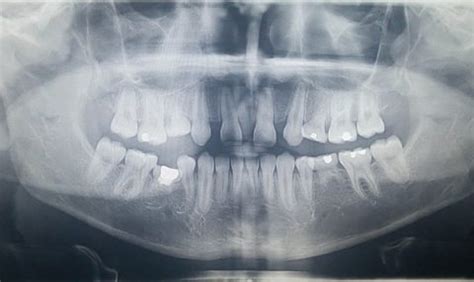

- Se detecta por ortopantografía.

Siempre tendrá que ser valorado por el dentista. Lo habitual es que se realice una prueba de imagen como la ortopantografía. Según su sospecha, puede solicitar otras pruebas de imagen.